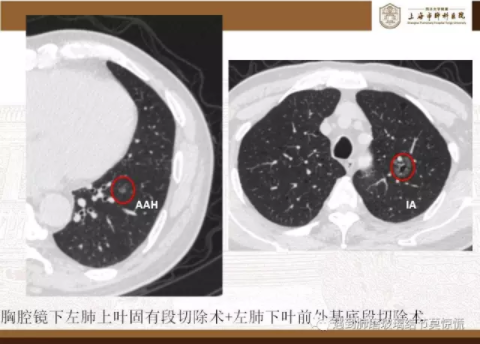

下面就我们的病例分析一下怎么进行肺段切除。

MIA= 微浸润腺癌   IA= 浸润性腺癌   AIS= 原位腺癌   AAH= 不典型腺瘤样增生